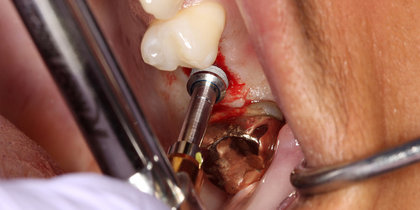

• Glidewell HT Implants are immediately placed into extraction sites in the areas of tooth #3 & #4. thumbnail image

Extraction with Immediate Placement

Glidewell HT Implants are immediately placed into extraction sites in the areas of tooth #3 & #4.